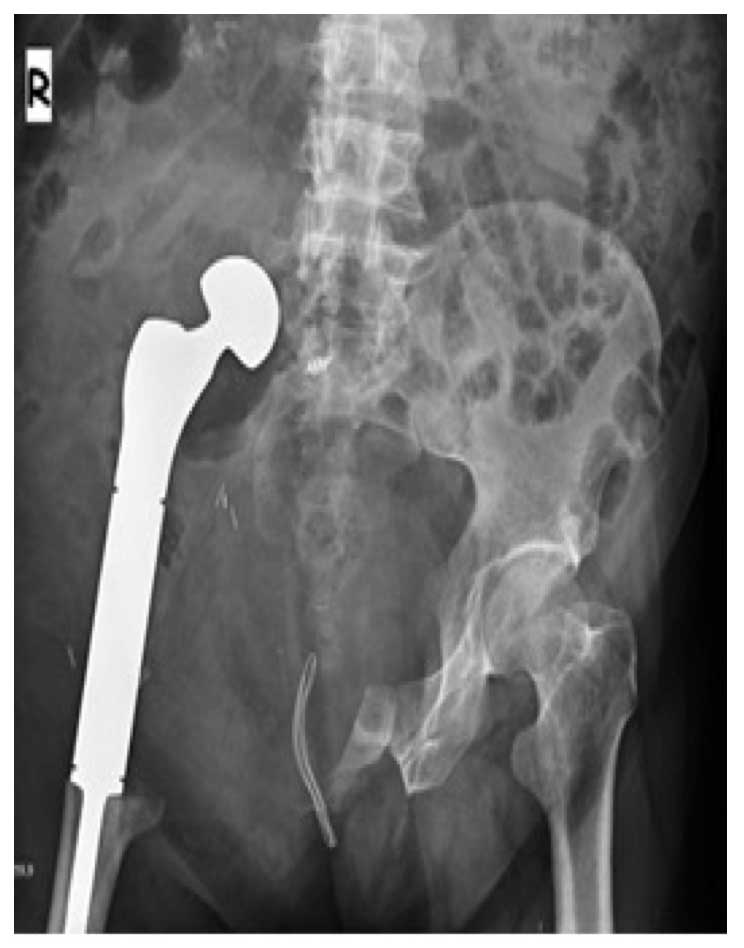

Hastaya internal hemipelvektomi yapılmış, proksimal femur tümör protezi ile kalça transpozisyonu gerçekleştirilmiştir.

Ameliyat Sonrası: Hemipelvektomi sonrası proksimal femur kalça protezi ile kalça transpozisyonu görülmekte.